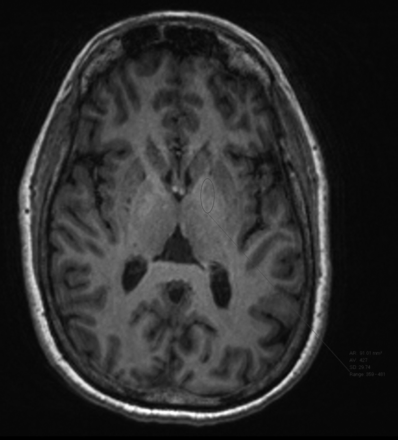

Two radiologists conducted a quantitative analysis of unenhanced T1-weighted images using ROI measurements. Measurements were made on the baseline scan and the seventh scan. In keeping with previously described techniques, ROIs were drawn over the left globus pallidus, dentate nucleus, lateral ventricle, and pons, and average signal intensity was recorded.12,19 Examples of ROI selection are presented as Figs 1⇓–3. We compared DN and GP signal intensities with T1 measurements of the pons and calculated the ratios of these intensities: dentate nucleus/pons (DN/pons) and globus pallidus/pons (GP/pons).12 If the left side could not be evaluated due to artifacts or pathology, the right side was used.

Globus pallidus ROI selection.